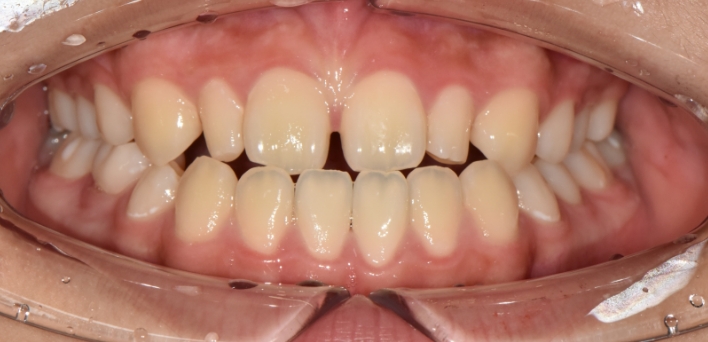

※ 더서울치과의원은 의료법을 준수하며 위 케이스는 실제 환자의 동의를 얻은 사례로 치료 전, 후가 동일한 환경에서 촬영되었습니다.

환자 케이스에 따라 부작용이 발생할 수 있습니다. 이 부분은 의료진의 충분한 상담과 체크를 통해 예방하고 줄일 수 있습니다.

[심미치료 부작용] 시술 후 치아 시림, 보철물 파손 등의 부작용이 발생할 수 있어 개인별 치아 상태에 따른 정확한 진단과 사후 관리가 중요합니다.